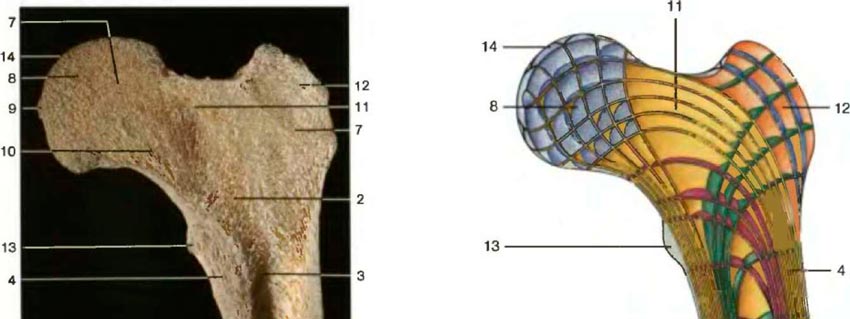

| Срединный разрез через проксимальную часть бедренной кости взрослого человека, показывающий структуру распределения губчатого вещества | Трехмерное изображение векторных линий головки бедренной кости (по Б. Куммер) |

| Кости скелета состоят из двух различных частей: губчатого и компактного вещества. Перекладины губчатого вещества хороню приспособлены к механическим воздействиям, показанным векторными структурами. Пространство между перекладинами заполнено костным мозгом, зоной кроветворения. На компьютерной и магнитно-резонансной томограммах изображения костей, мышц и мягких тканей различны. Изображение при компьютерной томографии аналогично рентгеновскому, поэтому зоны максимального накопления, например кости, белого цвета, а зоны минимального накопления, например жировая ткань, - черного цвета. По контрасту интенсивность сигнала при магнитно-резонансной томографии, получаемая при помощи магнитного воздействия, а не рентгеновских лучей, очень сильно отличается, и плотные участки костей выглядят черными, а мягкие ткани, такие как костный мозги жировая ткань, - белыми (для сравнения смотрите рисунки). Надкостница имеет сильно развитую сеть нервных волокон и является структурой, необходимой для питания костей, их кровоснабжения, роста и репарации. | |||

| Венечный разрез через проксимальный эпифиз большеберцовой кости взрослого человека. Видна зона уплотнения кости на месте бывшей эпифизарной пластинки (пунктирная линия) |

Структура костей скелета (по Беннингхоффу). Видно, что компактное вещество кости имеет пластинчатое строение содержит гаверсовые пластины и каналы |